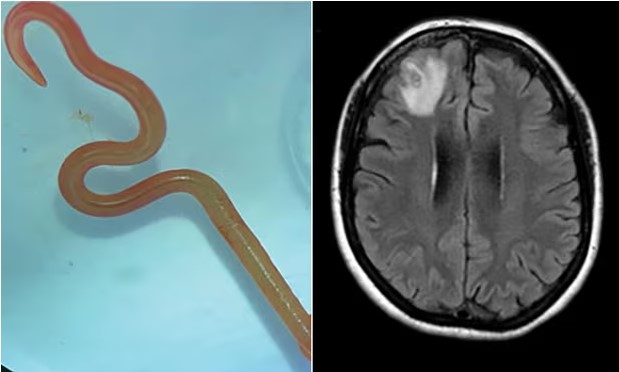

Unutkanlık ve depresyon şikayeti ile hastaneye giden kadının beyninde 8 santim uzunluğunda canlı solucan bulundu.

Kanberra Hastanesi'nde enfeksiyon hastalıkları uzmanı Dr. Sanjaya Senanayake, nörocerrah meslektaşı Dr. Hari Priya Bandi'yi telefonla arayıp hastasının beyninden 8 cm uzunluğunda canlı bir yuvarlak solucan çıkardığını söyledi ve daha fazla adım atmadan önce Senanayake ve diğer hastane çalışanlarından tavsiye istedi.

64 yaşındaki hastanın beyninde yapılan manyetik rezonans görüntüleme (MRG) taraması, ameliyat gerektiren anormalliklerin olduğunu gösterdi. Ancak nörocerrah Bandi, bu tür bir durumu hiç beklemiyordu. Bandi, "Nörocerrahlar sık sık beyindeki enfeksiyonlarla uğraşırlar, ancak bunun bir solucan olacağını düşünmek bile akıllarına gelmezdi," dedi.